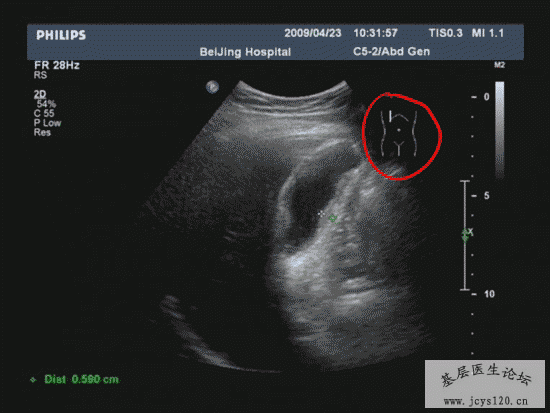

医学教育网讲义里面的精彩图片!